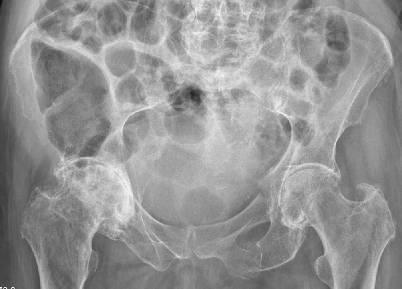

Im Verlauf stellte sich nach der vorliegenden Dokumentation (Tab. 1) ein Delir ein, das sich mit Desorientiertheit, Halluzinationen (die Patientin führte Selbstgespräche), psychomotorischer Unruhe wie Nesteln und teilweiser Somnolenz präsentierte. Die Symptome waren v. a. nachts stark ausgeprägt, zusätzlich zu Angstzuständen. Eine neuroleptische Therapie mit Quetiapin, die kontinuierlich gesteigert wurde, brachte eine gewisse Besserung. So war Frau K. teilweise wieder imstande, Angehörige bei ihren Namen zu nennen. Das am 28.12.2015 durchgeführte CT (Computertomographie) vom Becken zeigte neben der vorderen Acetabulumfraktur links eine Dislokation der unteren Schambeinastfraktur links und eine zusätzliche Fraktur des Sakrums ohne Beteiligung der Neuroforamina (Abb. 1). Wegen der komplexen Situation wurde Frau K. zur Weiterbehandlung auf die akutgeriatrische Abteilung überwiesen.

Abb. 1

Schwere Koxarthrose rechts, vordere Acetabulumfraktur links, Dislokation der unteren Schambeinastfraktur links, Fraktur des Sakrums